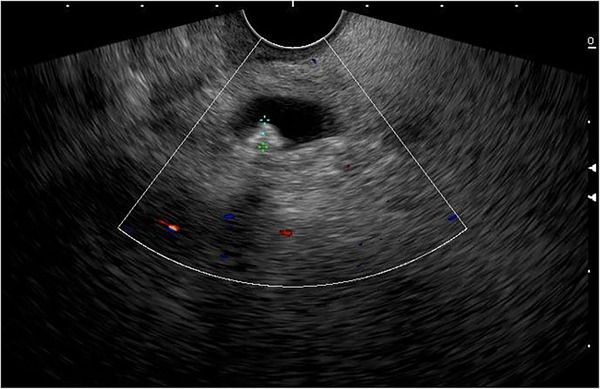

Patients with ascending cholangitis underwent ERCP to determine the underlying cause of CBD obstruction. Sphincterotomies and stone extractions were performed if CBD stones were identified using standard techniques using a duodenoscope (Model TJFQ‐190 V; Olympus Optical Corporation or Model ED‐580XT; Fujinon Corporation). Patients with a CBD stone on US/cross‐sectional imaging or a TB >4 mg/dL with a dilated CBD on US/cross‐sectional imaging initially underwent EUS. All EUS procedures were performed by one of six experienced endosonographers (Siriboon Attasaranya, Jirat Jiratham‐opas, Tanyaporn Chantarojanasiri, Apichet Sirinawasatien, Kannikar Laohavichitra, and Thawee Ratanachu‐ek; each with experience performing more than 1000 EUS examinations for pancreatobiliary diseases). The EUS examinations were performed with an electronic radial or linear EUS scope by Olympus (Model GF‐UCT 180; Olympus Optical Corporation) with Aloka Arietta 850 ultrasound processor or Fujinon (Model EG‐580 UT; Fujinon Corporation) with SU‐1‐H ultrasound processor. CBD stones were defined as echogenic material or hyperechoic lesions, with or without posterior acoustic shadow on EUS (Figure 1). If CBD stones were present, the patients underwent ERCP for stone extraction in the same session of EUS.